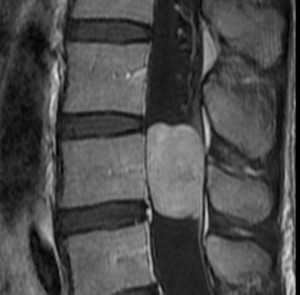

(Слева) Аксиальный срез, Т1-ВИ: крупная остеохондрома, исходящая из остистого отростка L4, центральное костномозговое пространство характеризуется гиперинтенсивностью сигнала, периферический хрящевой колпачок гипоинтенсивен. В области правого подвздошного гребня видна остеохондрома более классического вида «цветной капусты».

(Справа) Аксиальный КТ- срез, пациент с ВМЭ: визуализируется небольшой костный вырост в области левого корня дуги позвонка с признаками кортико-медуллярной непрерывности с подлежащей костью.